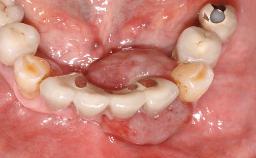

Surgical treatment of a 32-year old, healthy and non-smoking female who required removal and replacement of a lateral maxillary incisor due to internal root resorption. The inflammatory process caused a reduction of the crestal bone level on the distal side of the tooth necessitating an augmentation procedure to meet the patient's high esthetic demands. Due to the high smile line, the thin soft-tissue biotype and triangular-shaped teeth several esthetic risk factors are present.

After flapless tooth removal and a healing period of 6 weeks a diameter-reduced two-piece implant is placed. The bone defect on the facial aspect is corrected with a contour augmentation using autologous bone chips covered with DBBM particles and a collagen membrane according to the Guided Bone Regeneration (GBR) approach.

Type of Implants Reduced-Diameter|Two-Piece